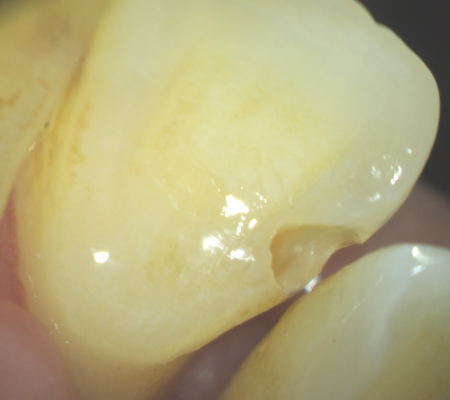

今まで、歯科治療において手探りともいえる外科の歯科治療だと感じていました。それは、口の中とは見えそうでよく見えないところが多く、照明をあてたとしても暗くて、また狭く、陰に隠れてしまう部分が多いです。

実際に診に見えないところを、レントゲンを参考に想像しながら、経験と勘で治療していたといっても過言ではありません。 しかしマイクロスコープ(顕微鏡)を使うと確実に肉眼で見ながら治療できるようになり、とても精度の高い、成功率の高い歯科治療ができるようになります。